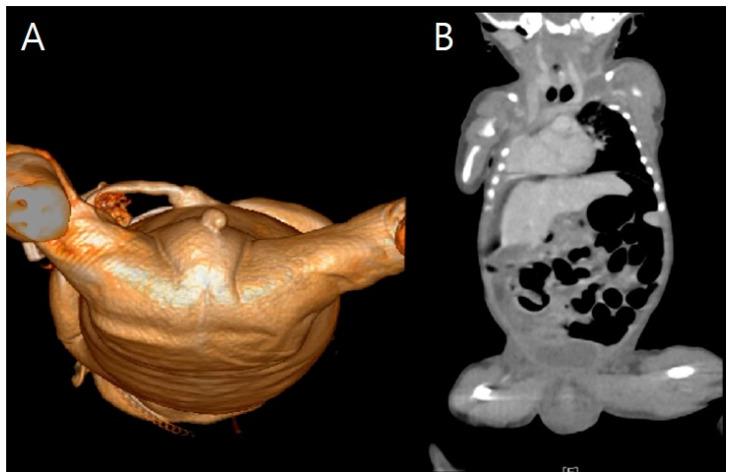

: VACTERL association is a widely known congenital malformation that includes vertebral, anal, cardiac, tracheoesophageal, renal, and limb anomalies. Patients with VACTERL and hydrocephalus appear to form a distinct group, both genetically and phenotypically, and their condition has been called VACTERL-H syndrome. Most cases of VACTERL-H have been reported postnatally, as VACTER-H syndrome is difficult to diagnose prenatally. Here, we report a case of VACTERL-H syndrome in a dichorionic and diamniotic twin diagnosed prenatally by ultrasonography and confirmed postnatally by three-dimensional computed tomography (3D CT). A 34-year-old multiparous female was referred to our institution at 31 + 3 weeks gestation for suspected fetal ventriculomegaly. Detailed examinations using two-dimensional and Doppler ultrasounds revealed hydrocephalus, bilateral dysplastic upper arms, radial aplasia, unilateral pulmonary agenesis, dextrocardia with right atrial enlargement, a unilateral hypoplastic ectopic kidney, a single umbilical artery, a tracheoesophageal fistula with a small stomach, polyhydramnios, and anal atresia. Findings from the postnatal 3D CT aligned with the prenatal diagnosis, showing upper-limb agenesis, dextrocardia with pulmonary hypoplasia, tracheoesophageal fistula, imperforate anus, and colon dilatation. The affected 1390-g male twin had an unaffected 1890-g female twin sister and a healthy 6-year-old brother. : Upon encountering fetuses with multiple anomalies, including ventriculomegaly, a small stomach with polyhydramnios, an abnormally positioned heart, and upper-limb abnormalities, clinicians should perform systematic ultrasonographic examinations to detect associated anomalies and be aware of VACTERL-H syndrome.

VACTERL 协会是一种广为人知的先天性畸形,包括脊柱、肛门、心脏、气管食管、肾脏和肢体异常。患有 VACTERL 和脑积水的患者似乎在遗传和表型上形成了一个独特的群体,他们的病情被称为 VACTERL-H 综合征。大多数 VACTERL-H 病例都是在产后报告的,因为 VACTERL-H 综合征很难在产前诊断。在这里,我们报告了一例产前通过超声诊断并通过三维 CT 产后证实的双绒毛膜和双羊膜性双胞胎 VACTERL-H 综合征病例。一位 34 岁的多产妇在 31+3 周妊娠时因疑似胎儿脑室扩大被转诊至我们机构。使用二维和多普勒超声进行的详细检查显示脑积水、双侧发育不良的上臂、桡骨发育不全、单侧肺发育不全、右心房扩大的右位心、单侧发育不良的异位肾、单脐动脉、伴有小胃的气管食管瘘、羊水过多和肛门闭锁。产后的 3D CT 检查结果与产前诊断一致,显示上肢发育不全、肺发育不全的右位心、气管食管瘘、肛门闭锁和结肠扩张。受影响的 1390 克男性双胞胎有一个未受影响的 1890 克女性双胞胎妹妹和一个健康的 6 岁弟弟。